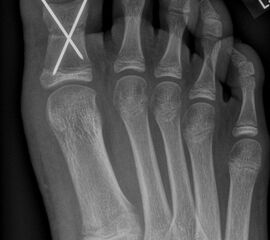

Abb. 2 a-c: offene Wachstumsfugen MT I Basis und Zehen (a), teilweise geöffnete Wachstumsfugen (b) und geschlossene Wachstumsfugen (c).

Die erforderlichen Osteotomien sind daher dem Fugenverlauf anzupassen, diese sind unbedingt zu respektieren. Wird eine Wachstumsfuge versehentlich mit der Fräse verletzt, kann durch partiellen oder kompletten Fugenverschluss ein Fehlwachstum provoziert werden. Achsabweichungen oder ein Wachstumstopp der betroffenen Region können die Folge sein. Offene Wachstumsfugen begrenzen die Osteotomieausrichtung besonders im Bereich des dorsalen Calcaneus, der Metatarsale I Basis und der IV. oder V. Zehe im End- und Mittelglied.

Zusätzlich schränken Wachstumsfugen die Wahl der Osteosynthese ein. Eine die Fuge kreuzende Osteosynthese ist ausschließlich mit Kirschner-Drähten möglich (Abb. 3).